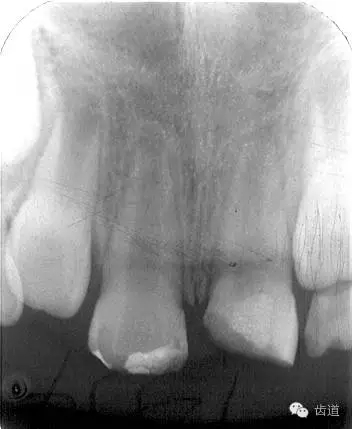

術(shù)前

術(shù)后

術(shù)后199日

術(shù)后1084日